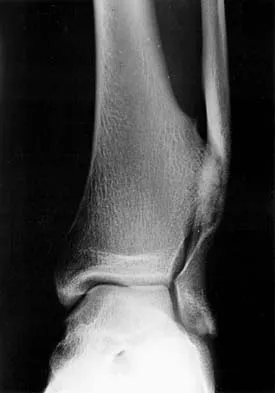

An 11-year-old boy has had a fever and pain and swelling over the lateral aspect of his right ankle for the past 3 days. Examination reveals warmth, swelling, and tenderness over the lateral malleolus, and he has a temperature of 103.2 degrees F (39.5 degrees C). Laboratory studies show a WBC count of 13,200/mm3 with 61% neutrophils, an erythocyte sedimentation rate of 112 mm/h, and a C-reactive protein of 15.7. Radiographs and a T2-weighted MRI scan are shown in Figures 13a through 13c. Aspiration yields 1 mL of purulent fluid. Management should now consist of

Explanation

The initial signs and symptoms of acute hematogenous osteomyelitis vary widely but usually include fever, bone pain, and impaired use of the involved extremity. In lower extremity infections, the child may limp or refuse to walk. Examination often reveals bone tenderness. In more advanced cases, erythema, warmth, and swelling may be present. The WBC and neutrophil counts are not always elevated, but the erythocyte sedimentation rate will be abnormal in more than 90% of patients. When the infection is diagnosed early, before a subperiosteal abscess has formed, antibiotics alone may be adequate to treat the infection. This patient has a more advanced infection, however, with the MRI scan revealing a subperiosteal abscess that was confirmed by aspiration. When an abscess is present, surgical drainage is generally indicated to remove devitalized tissue and to enhance the efficacy of the antibiotics. Further studies, such as bone or indium scans, are not necessary and will delay definitive treatment. Scott RJ, Christofersen MR, Robertson WW Jr, et al: Acute osteomyelitis in children: A review of 116 cases. J Pediatr Orthop 1990;10:649-652.